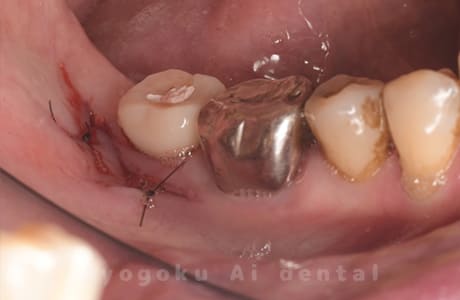

Case12

-

- 原因

- 左下7番歯牙破折

- 治療内容

- インプラント治療

- 治療費用

- 約600,000円

左下の奥歯が痛いとのことでご来院された患者様です。歯が完全に割れており、保存が不可能であったため、抜歯を行い、その際に骨に変わるお薬を入れ、十分な治癒を待ってからインプラント治療を行いました。経過良好で、大変満足されました。

<リスク・副作用>

治療後、痛みや違和感、出血、腫れなどが出る事があります。喫煙者、糖尿病などの方の場合、歯が生着しない場合があります。